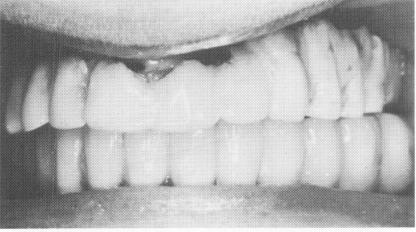

Fig. 11-128. Six days later the tissues had healed sufficiently around the implants to allow removal of the sutures. The inflammation of the anterior soft tissues was caused by the impingement from the ill-fitting temporary splint.

Fig. 11-129. In order to finish the prosthesis as rapidly as possible, the copings were fitted at this very same visit.

Fig. 11-131. Five days later (11 days postoperatively) the one-piece metal casting was fitted over the abutments.